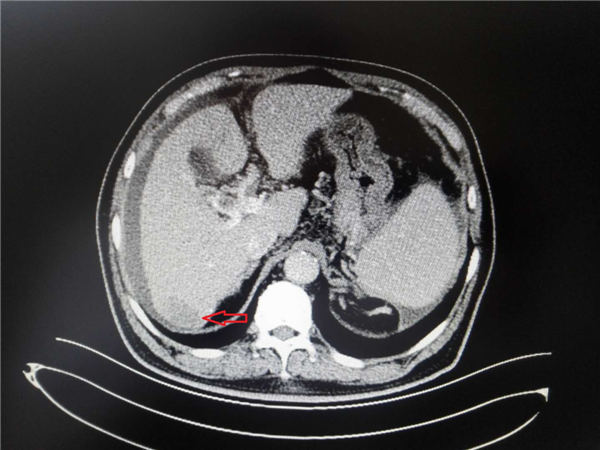

再利用球囊扩张,进行肝内穿刺道(如下图,红箭头所示为穿刺道压迹)。